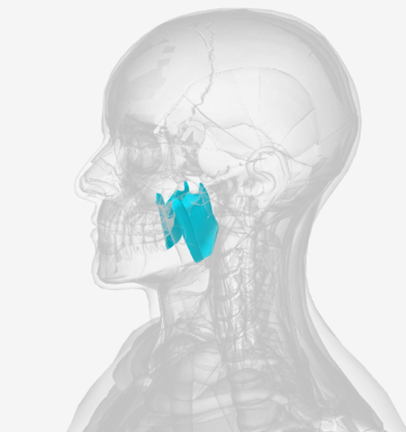

Tensor veli palatini

origin is on the sphenoid bone, coursing down to a tendon wrapping down around the pterygoid hamulus (of the sphenoid), then directed medially to the palatal aponeurosis; function is to dilate the Eustachian tube

Pterygoid hamulus

D